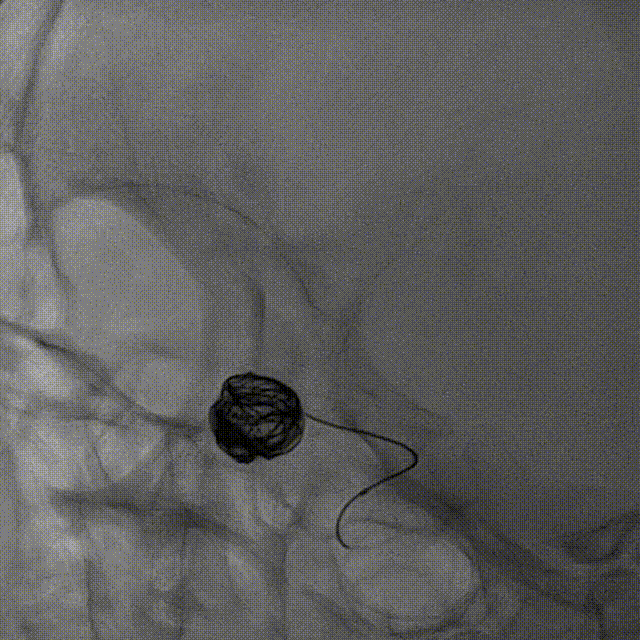

释放弹簧圈:

支架释放后,使用弹簧圈微导管释放弹簧圈,填塞动脉瘤。

术后即刻造影

术后即刻造影,正侧位造影示载瘤动脉血流通畅,各主要分支血管显影良好,瘤腔内未见造影剂残余。